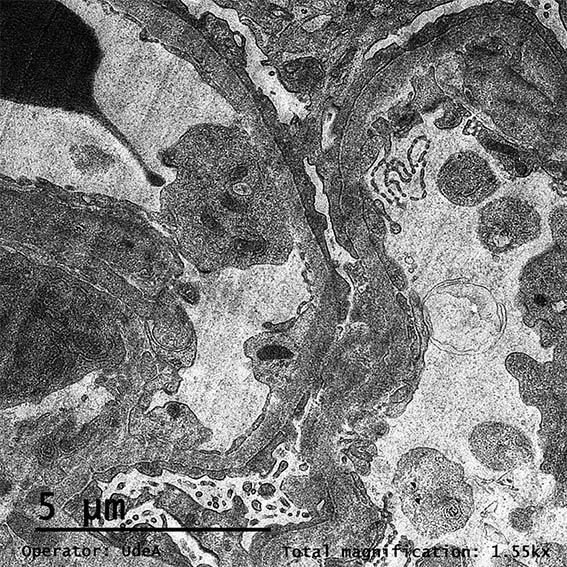

Figura 8. ME, aumento original, X2.100.

Figura 9. ME, aumento original, X2.100.

Figura 10. ME, aumento original, X2.100.

Figura 11. ME, aumento original, X3.000.

Figura 12. ME, aumento original, X3.000.